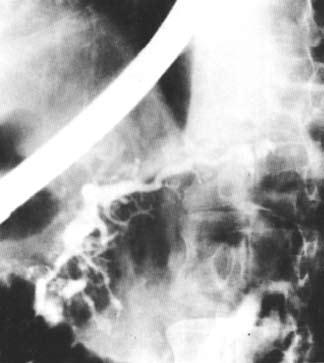

Ретроградная холангиопанкреатикография (РХПГ), позволяющая контрастировать вирсунгов проток, выполняется в ходе эндоскопического исследования (подробнее см. ниже) (рис. 132).

Рис. 132. Ретроградная панкреатикография при хроническом панкреатите. На снимке виден резко расширенный главный панкреатический проток